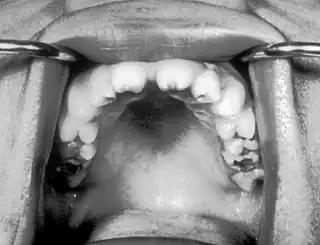

![]() Incisivos con muescas conocidos como dientes de Hutchinson que son característicos de la sífilis congénita | ||

- Dientes incisivos superiores romos conocidos como dientes de Hutchinson ¨

Un grupo de síntomas que se encuentra con frecuencia es la tríada de Hutchinson, que consiste en dientes de Hutchinson (incisivos con muescas), queratitis y sordera y ocurre en el 63% de los casos.[5]

- Tríada de Hutchinson, un conjunto de síntomas que consisten en sordera, dientes de Hutchinson (incisivos centrales superiores en forma de clavija con muescas centrales y muy espaciados) y queratitis intersticial, una inflamación de la córnea que puede provocar cicatrización corneal y ceguera potencial

- Molares de Mulberry (primeros molares permanentes con múltiples cúspides mal desarrollados)[7]